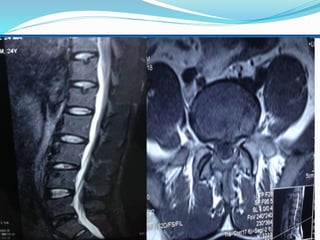

Inclusion Criteria’s:

1. Small to medium sized contained protruded

intervertebral disc herniations confirmed by MRI.

Inclusion Criteria’s: 1. Smallto medium sized contained protruded intervertebral disc herniations confirmed by MRI. 2. Back pain of discogenic origin, with or without pain to specific dermatomal distribution that limits the activity for at least 6 weeks not relieved by conservative treatments. 3. Neurogenic claudication. 4. Neurogenic findings referring to a single nerve root involvement positive lasegue sign,(decreased tendon reflex, sensation and motor response).